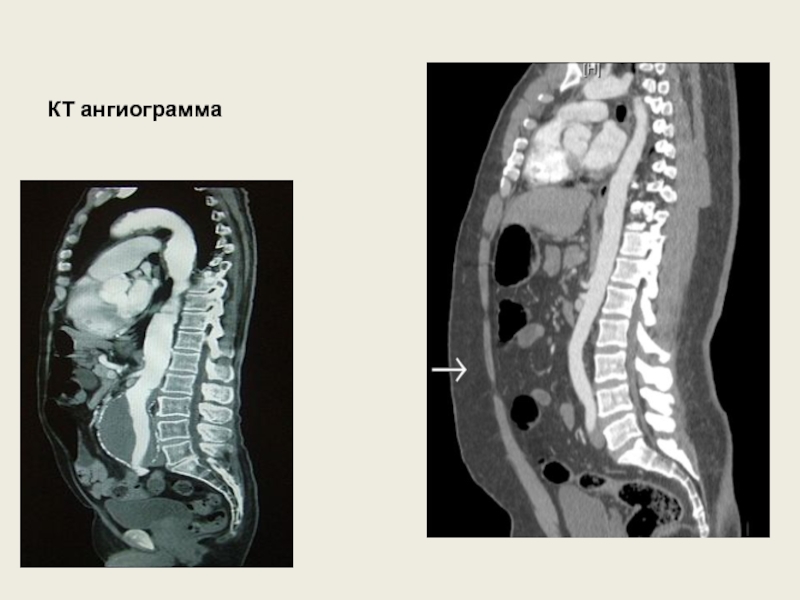

Слайд 27КТ ангиограмма

КТ ангиограмма